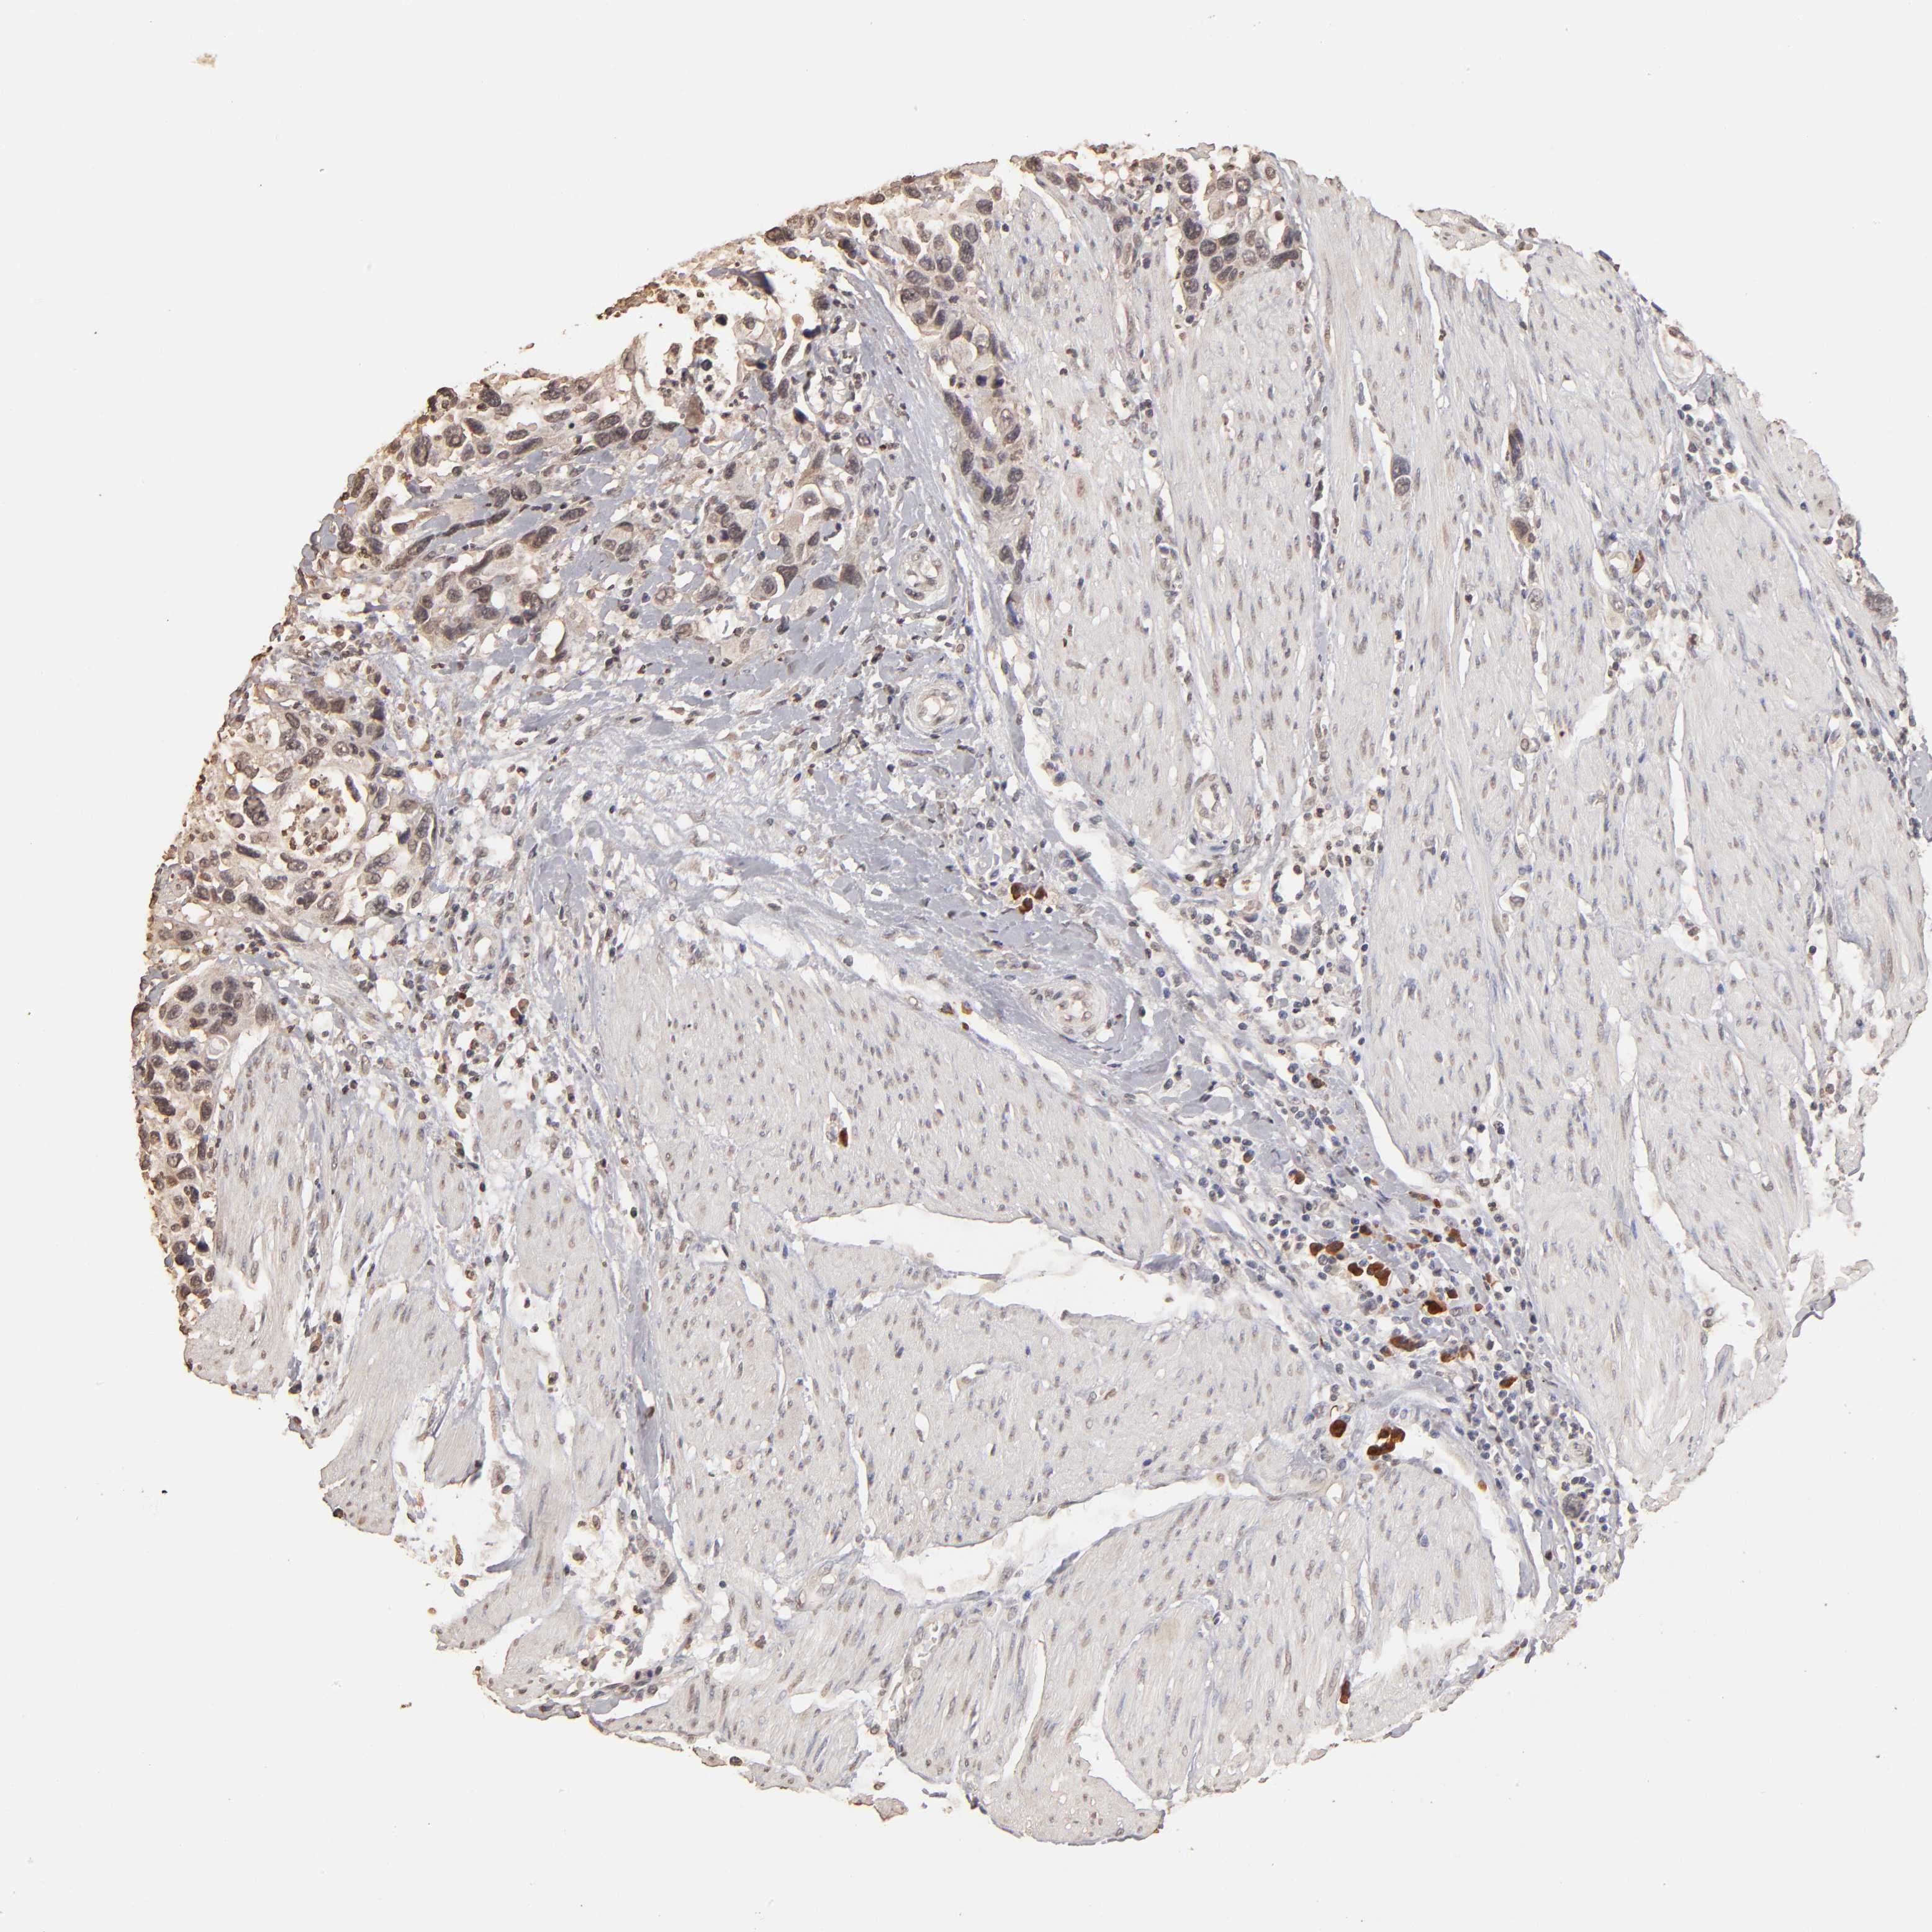

UROTHELIAL CANCER - Protein expressioni

A mouse-over function shows sample information and annotation data. Click on an image to view it in a full screen mode. Samples can be filtered based on level of antibody staining by selecting one or several of the following categories: high, medium, low and not detected. The assay and annotation is described here.

Note that samples used for immunohistochemistry by the Human Protein Atlas do not correspond to samples in the TCGA dataset.

Antibody stainingi

Antibody staining in the annotated cell types in the current human tissue is reported as not detected, low, medium, or high, based on conventional immunohistochemistry profiling in selected tissues. This score is based on the combination of the staining intensity and fraction of stained cells.

Each image is clickable and will lead to virtual microscopy that enables deeper exploration of all samples and also displays staining intensity scores, fraction scores and subcellular localization as well as patient and tissue information for each sample.

Antibody HPA002919

Staining

High

Medium

Low

Not detected

Intensity

Strong

Moderate

Weak

Negative

Quantity

>75%

75%-25%

<25%

None

Location

Nuclear

Cytoplasmic/membranous

Cytoplasmic/membranous,nuclear

Urothelial carcinoma, High grade

Urothelial carcinoma, Low grade

Adenocarcinoma, NOS